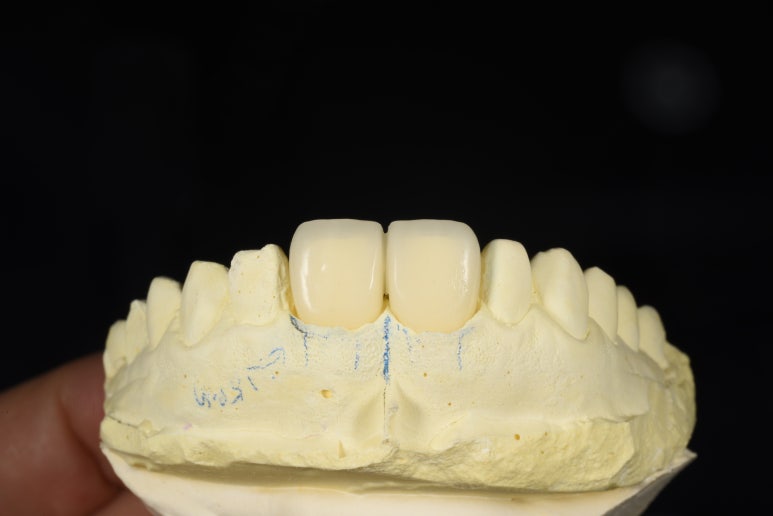

1. 임시치아 제작

먼저 현재 상태에서 본을 떠 기공소에 의뢰했고,

BOPT 컨셉에 맞는 임시치아를 제작했습니다.

임시치아 제작과정

크라운 제작과정

완성된 크라운